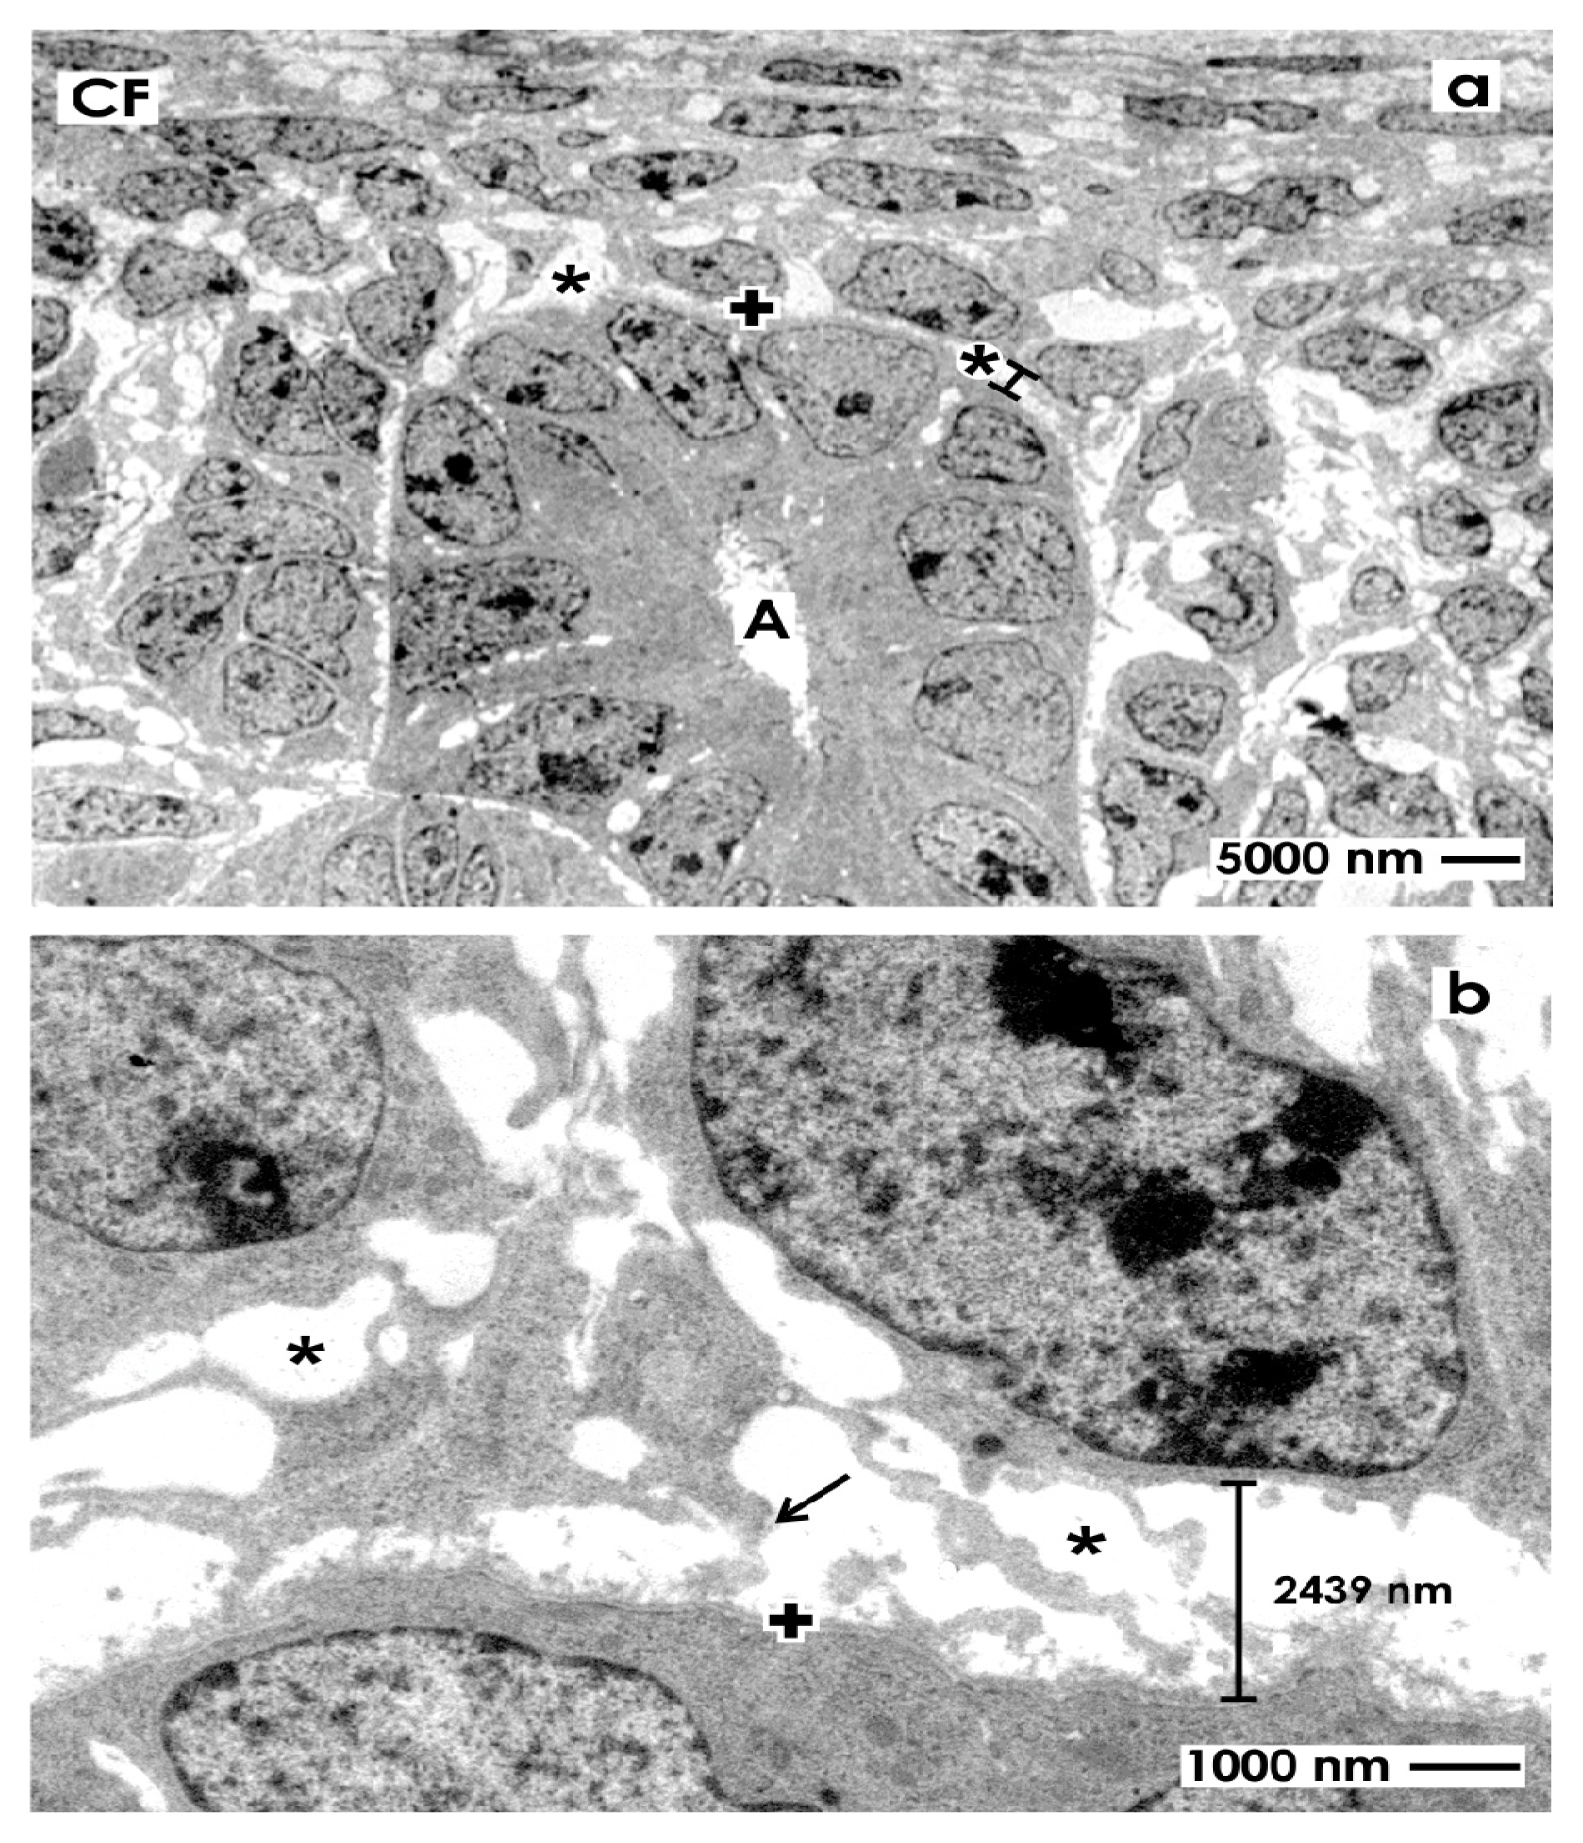

2.3. Electron Microscopical View to the Renal Stem/Progenitor Cell Niche

2.3.1. Traditional Fixation with Glutaraldehyde (GA)